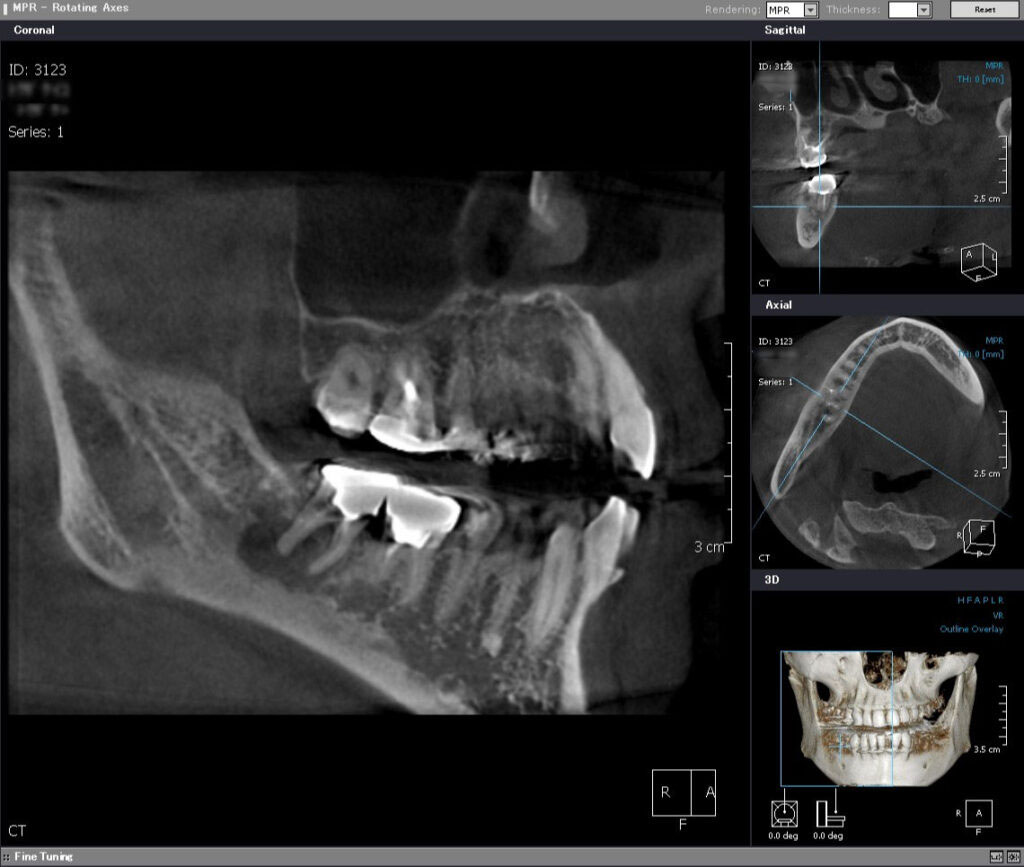

術前CT矢状断

近遠心的(手間から奥に向かって)に、根っこの先に化膿による大きな鶏卵状の境界明瞭な黒い骨透過像を認める。ここまで大きいと一般的には抜歯が適応と言える。

根っこの先の黒い骨透過像(吸収像)をはっきりと認め、下顎の神経束(丸い玉状の像)ギリギリまで拡がっていることがわかる。このままにしていれば、顎の痺れが出現すると考えらえる。